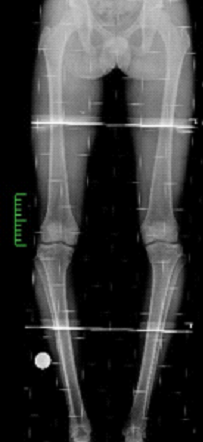

Dr.Jijeesh Dr.Jijeesh HTO is a surgical procedure used to correct the Tibial varus deformity. It is done in genu varus or bowleg. Bowleg is a condition in which the legs have a gradual or sudden bent due to various reasons. The term varus means bent inwards and the term valgus means bent outward Normally, on standing both the knees bear equal weight. And in the knee the weight distribution is more on medial or inner side than outer side. So any increase in small degree of varus will cause more force on the medial side than lateral side. In case of valgus small degree wont have much effect on the lateral side. When a person has bowlegs there is increased load on the inner side of the knee more commonly (Varus) or the outer side of the knee (Valgus). This increased loading causes that side to wear out faster and then presents as pain. Generally the body is able to compensate slight bow in the legs by the action of muscles. But when the bent is beyond a certain limit then the muscles cannot compensate and this results in reduction in the joint space and gradual worsening of the angle. When the cartilage of the joint wears out it is called reduced joint space or arthritis knee, which is due to overload. These arthritic changes are called secondary osteoarthritis Ie, arthritis due to bend or some secondary cause. Whereas primary osteoarthritis is the term used in case of wear and tear of knee joint due to old So, in these type of arthritis ie arthritis due to varus otherwise known as medial compartment osteoarthritis the treatment is to correct the alignment of the knee by doing a surgery called High Tibial Osteotomy. HTO is indicated not in all patients with genu Varus. Occasional pain that settles with rest doesn’t require surgery immediately. Generally, in about 80-90% people this settles down with proper exercises and medication for a few days. But if there is worsening on the x-rays even without much pain, then there is a role of correction of the deformity as a “preventive surgery”.

By changing the angle of bone the bow is corrected and the load-bearing axis or the mechanical axis of the limb is brought back to the center of the knee joint. This shift helps in taking the load off the affected side and relieves the pain, but more importantly it helps the overloaded side to get rest and heal. As the healing progresses the narrowed joint space again fills up cartilage. In HTO the principle is to cut the Tibia through a small incision (about 1.5 cm) few inches below the knee; an external fixator is applied to the bone; the angle is then gradually corrected by turning a nut on the fixator (1 mm per day) to a pre-defined point and the fixator is then locked. The fixator remains for a total of 3 months, because that is the time for the bone to heal and become solid. Once the bone healed the Fixator can be removed as an OPD procedure. And there is no. need of any second surgery. The second method is HTO using plate. Here instead of orhofix fixator plate is used for fixation of bone. The advantage is, there is no implant outside the body. But the disadvantage is to get a perfect alignment on standing weight bearing in all cases.